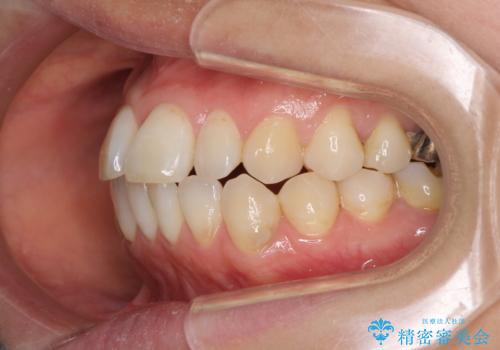

- 捻れた前歯と目立つ銀歯を気にして来院された患者様です。

歯列不正は軽微であったため、インビザライン・ライトにて改善することとしました。

左下大臼歯は根管治療が必要であったため、矯正治療前に根管治療を行い、その後矯正治療を行うこととしました。

矯正治療後には期にある銀歯を全てセラミッククラウンなどで補綴治療することとしました。

インビザライン・ライトによる矯正治療であったので、時間をかけずに治療を終えることができました。

口を開ける度に目立っていた銀歯もセラミックで自然な口元の印象となりました。